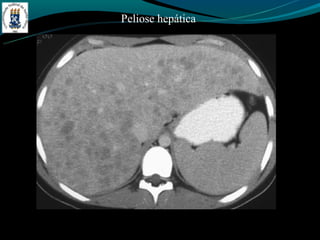

Peliose hepática